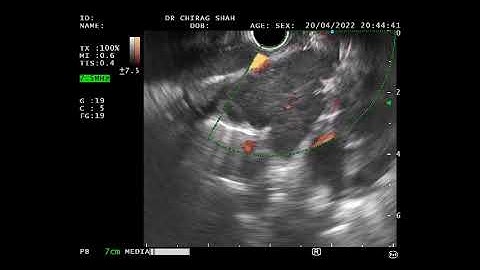

EUS-guided biopsy of lymph node to rule out lymphoma